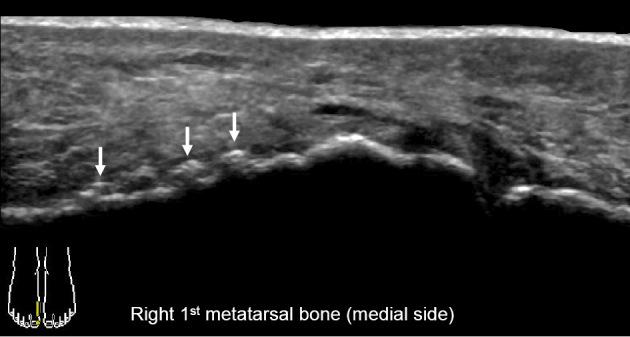

Musculoskeletal Ultrasound Manifestation of Osteoarthropathy in EMO Syndrome.

Intern Med. 2022 Jan 15;61(2):273-274. doi: 10.2169/internalmedicine.7106-21. Epub 2021 Jul 30.

DOI:10.2169/internalmedicine.7106-21

PMID:34334562

Musculoskeletal Ultrasound Manifestation of Osteoarthropathy in EMO Syndrome.EMO综合征中骨关节炎的肌肉骨骼超声表现